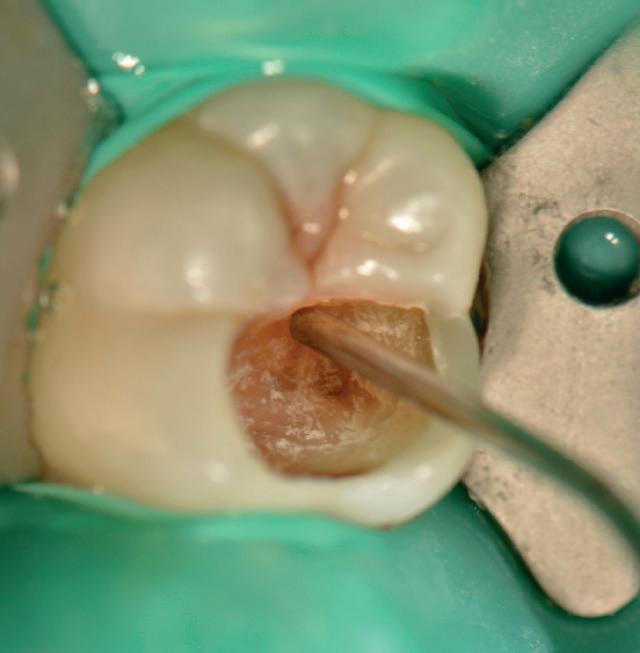

Predictable management of a deep carious lesion, page 27